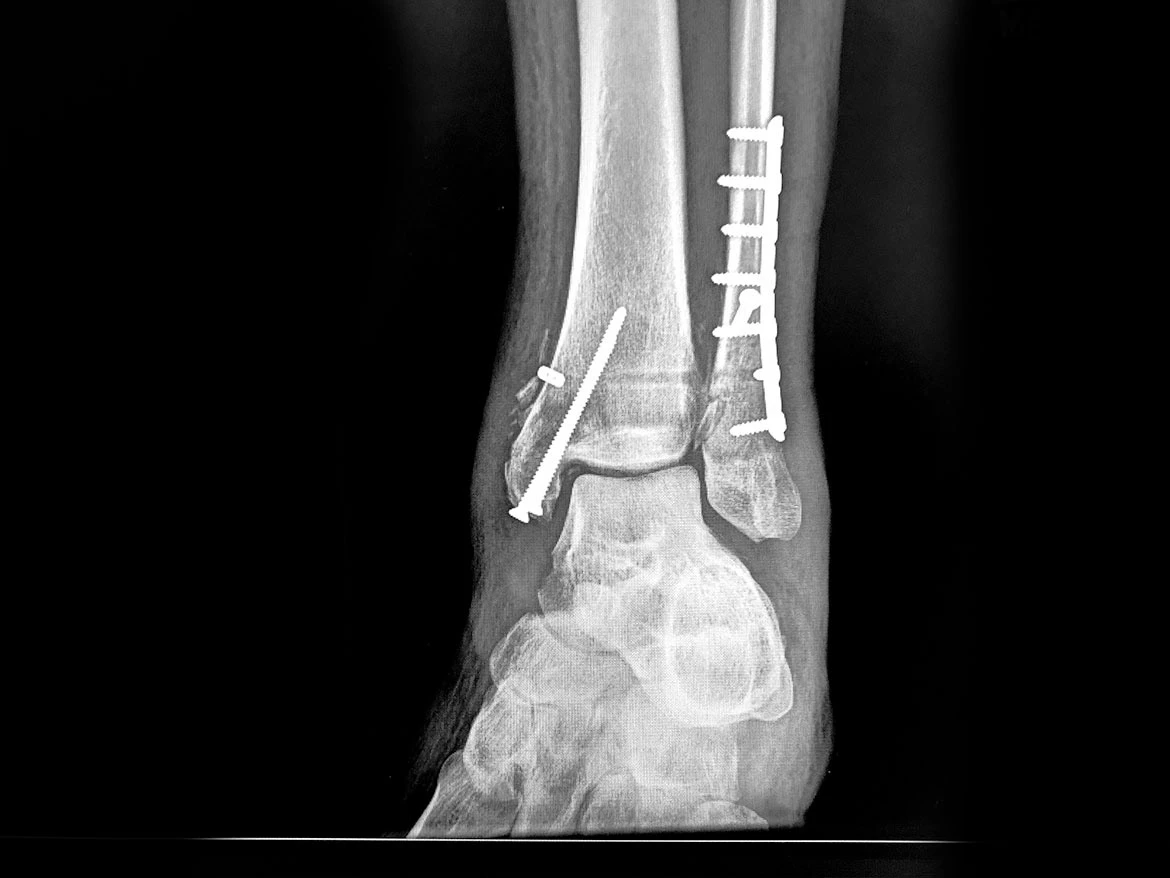

I broke my ankle socket on both sides, had a clean break on my tibia, broke my fibula and damaged ligaments. Like with my rescue, I am grateful to have been operated on by the best. Three months after the accident, I am walking two miles a day without the support of an ankle boot. Slowly. Per a suggestion from Matt of Expert Vagabond, I am including an X-Ray from a month after my injury. Coincidentally, on the night of my injury, I thought about Matt and the times that unexpected news challenges how we write about our travels, and I recalled the story of fellow travel writer Hank Leukart, who was rescued by helicopter after breaking his leg in New Zealand. Like with me, a Spot device aided in his rescue.

My ankle one month after broken ankle socket, tibia, and fibula.